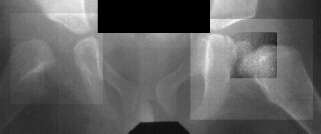

An

arthrogram at two years of age show irregular ossification of

the femoral head and dysplastic acetabulum,

but

the hip coverage is acceptable even in adduction.

The AVN will make a substantial limb length problem at maturity.